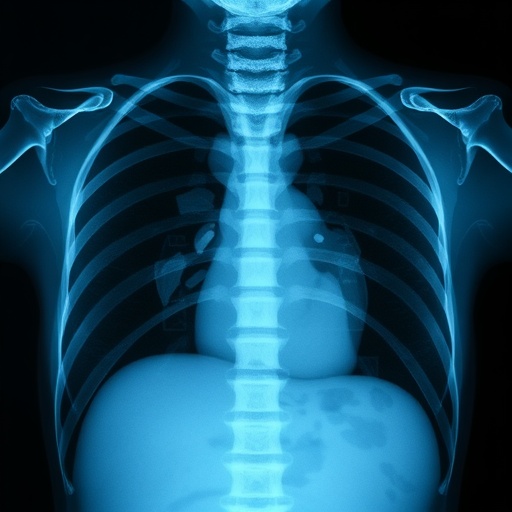

In recent years, the field of pediatric radiology has witnessed considerable advancements, particularly in the way neonatal chest radiographs are understood and executed. A fresh study conducted by Arulnathan, Jackson, and Howitt delves into the intricacies of anatomical marker placement in mobile neonatal chest radiographs, addressing both the challenges posed by standard medical practices and the practical implications on patient care.

The necessity for precision in neonatal radiography cannot be overstated. Newborns, especially those admitted to neonatal intensive care units (NICUs), face unique medical circumstances, and any misstep in radiographic planning can have significant repercussions. The authors emphasize that proper marker placement serves not merely as an academic exercise, but as a fundamental aspect of ensuring accurate diagnoses and effective treatment strategies.

Advances in technology have augmented the functionality of mobile radiography units, allowing for improved imaging quality. However, this also brings forth a set of challenges, particularly when dealing with vulnerable populations such as neonates. The study outlines how the intricate positioning of anatomical markers can be instrumental in enhancing the clarity of radiographic images while simultaneously adhering to the stringent standards set forth by radiological guidelines.

The significance of anatomical marker placement can also be seen through its impact on the interpretation of results. In medical imaging, clarity and context are vital. An incorrectly placed marker can lead to misinterpretation of a radiograph, thereby jeopardizing the medical decision-making process. By exploring alternative practices and innovative techniques for marker placement, the authors suggest that we can enhance the overall efficacy of neonatal imaging.